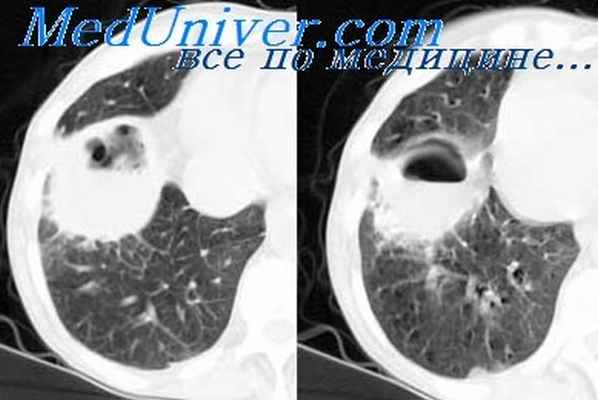

В последние годы в диагностике острых и хронических эмпием плевры все большее распространение получает ультразвуковое исследование, особенно при осумкованных, ограниченных эмпиемах, когда скопления жидкости маскируются массивными плевральными швартами и оказываются недоступными для рентгенологического распознавания. В ряде случаев при отграниченной гнойной полости возможно выполнение пункции и дренирования ее под контролем ультразвука. В трудных для диагностики ситуациях в первую очередь для выявления деструкции в легком используют компьютерную томографию.

В настоящее время с появлением современных методов лучевой диагностики при сложных ситуациях удаётся установить точный, достоверный диагноз. В нашей практике у 20 больных в сложных случаях заключительный диагноз установлен с применением рентгено-компьютерной томографии (РКТ). Применение РКТ позволяло детально оценить осумкованные выпоты, утолщение плевральных листков, очаговые образования в плевре.